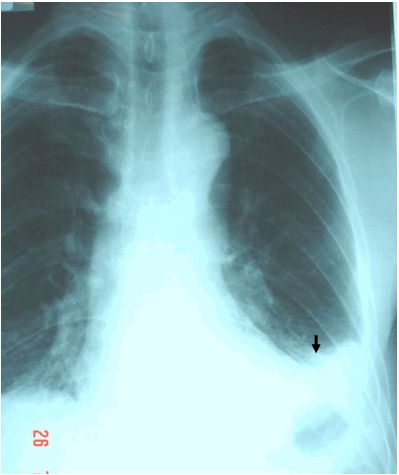

Tràn dịch màng phổi do lao trên hình ảnh

Tràn dịch màng phổi là số lượng bất thường của dịch xung quanh phổi. Tràn dịch màng phổi có thể do nhiều điều kiện y tế. Hầu hết tràn dịch màng phổi là không nghiêm trọng, nhưng một số cần điều trị để tránh các vấn đề.

Màng phổi là một màng mỏng phủ bề mặt của phổi và bên trong thành ngực bên ngoài phổi. Trong tràn dịch màng phổi, dịch tích tụ trong không gian giữa các lớp của màng phổi. Thông thường, chỉ 5ml chất lỏng có mặt trong khoang màng phổi, cho phép phổi di chuyển thuận lợi trong khoang ngực trong quá trình thở.